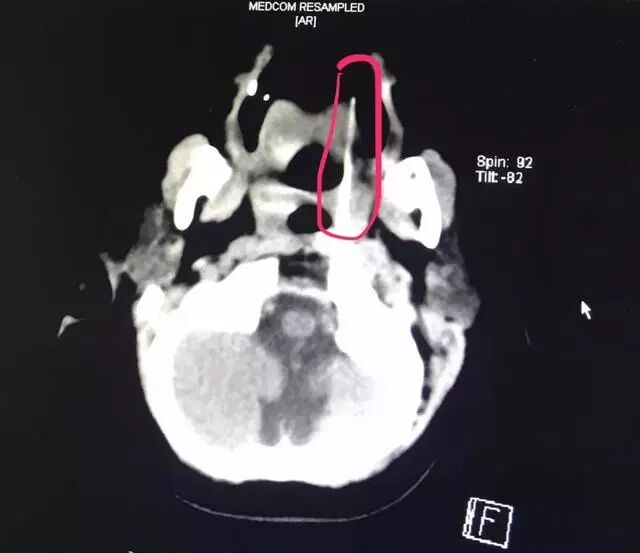

接診的醫(yī)護(hù)人員迅速為患兒安排了病床并實施了相關(guān)檢查。CTA檢查、顱腦CT、三維重建等一系列檢查顯示,長達(dá)13厘米的竹簽經(jīng)過小姑娘的口腔,直指環(huán)樞椎關(guān)節(jié)間隙,緊緊抵住人體最致命部位之一的椎動脈。

患兒的影像資料印證了醫(yī)務(wù)部孔心涓主任的擔(dān)心:

竹簽刺入的部位極其特殊而兇險,如果竹簽有一丁點挪動,可能會導(dǎo)致椎動脈被刺破,患兒就會有生命危險。